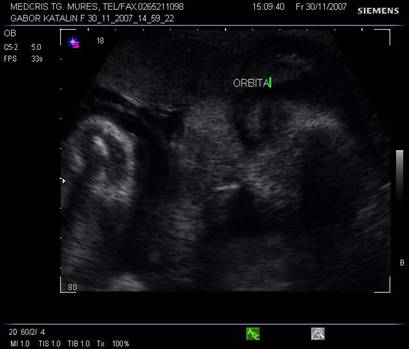

Dupa 13 saptamani in orbita apare si cristalinul in sectiunea parasagitala.

Fig. nr. 160 . Cristalinul hiperecogen, rotund in orbita dreapta .

Planul XIII - indica simultan orbitele si regiunea mandibulara, cristalinul apare ca un inel ecogenic in partea anterioara a orbitelor. Miscarile lente sau rapide ale ochilor pot fi cateodata evidentiate.

Planul XIV - plan oblic pentru orbite si nas.